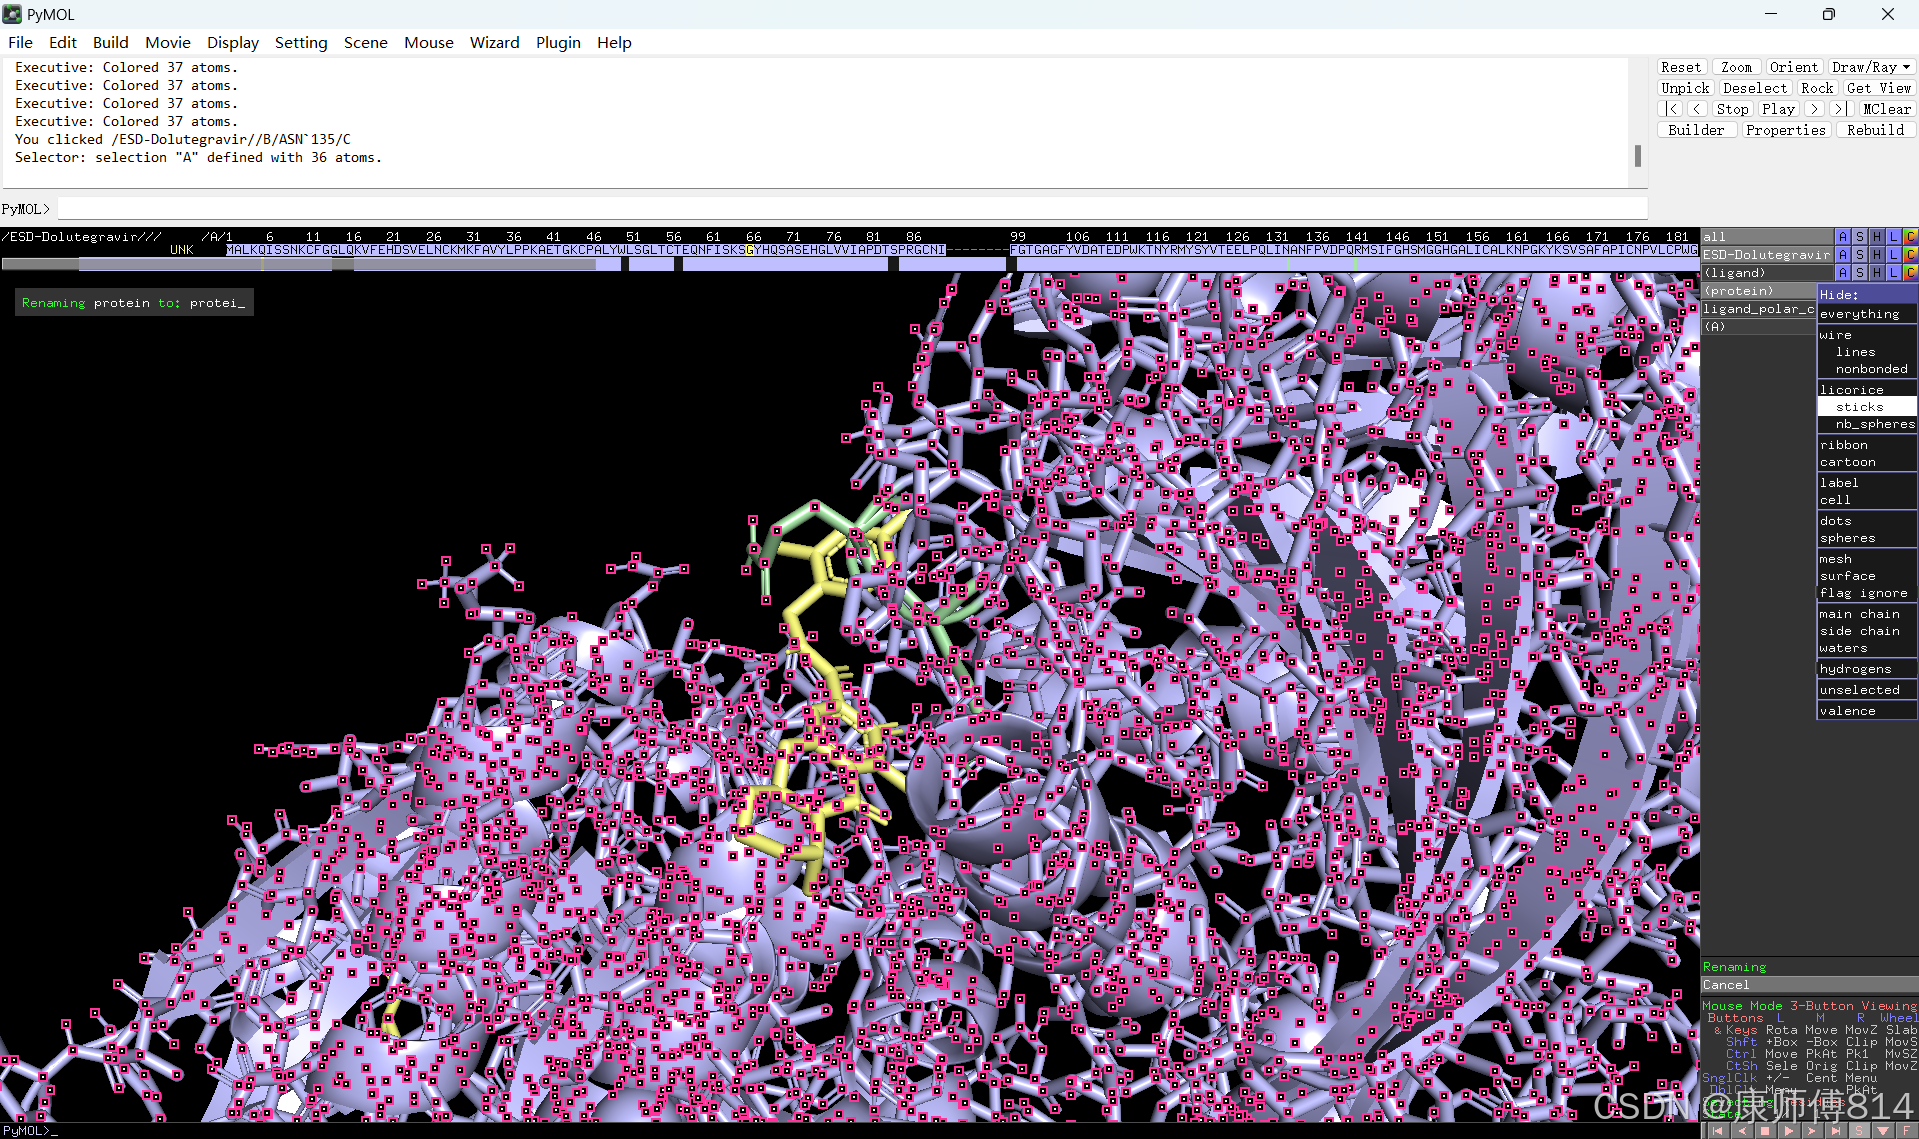

#接下来打开pymol操作

#在pymol中打开刚才得到的pdb文件,点击右下角S打开序列,选中小分子序列,命名为ligand。

#同样选中蛋白质序列,先将右下角Selecing选为Chains,然后才能悬着呢全部蛋白质序列(如果是多聚体蛋白,按住shift以连续选中多条链),命名为protein

#点击蛋白和小分子后的C按钮可以修改颜色

#选中小分子,按以下顺序点击以显示结合位点的氢键

#选中蛋白,点击show-sticks显示氨基酸棍状结构,右下角Selecting修改为Residues模式,选中与小分子连接的氨基酸残基,命名为A,并更改颜色

#点击蛋白,点击H-sicks隐藏蛋白棍状结构,然后显示小分子结合位点氨基酸残基棍状结构

#此时展示分子对接的基本要素已经形成,后续可根据需要修改背景颜色、显示氨基酸残基名字以及氢键键能等等,这里不再赘述

结果演示